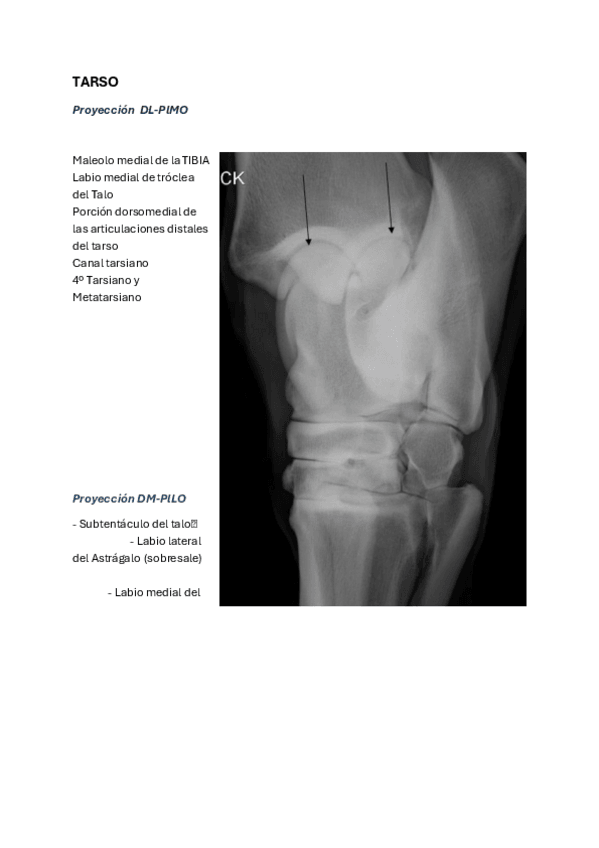

Imágenes de radiografias explicadas

He publicado nuevos apuntes de 3º Diagnóstico Por la Imagen: Imágenes de radiografias explicadas

Rx-miembro-pelviano.pdf

He publicado nuevos apuntes de 3º Diagnóstico Por la Imagen: CARPO-Y-TARSO-equi-y-perro.pdf